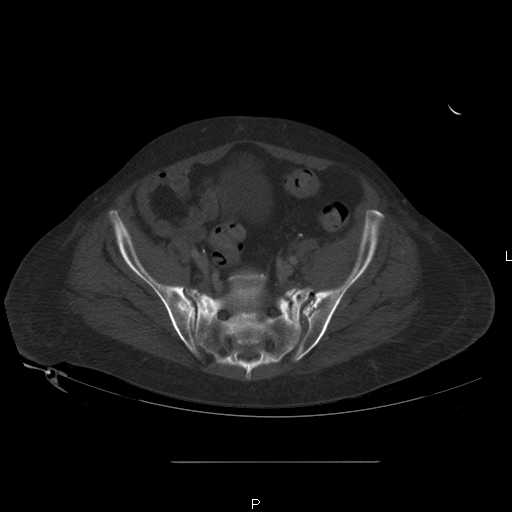

hello everyone, attached are images of a 59 yo female, admitted today after motor vehicle collision. Pt states her pelvis has been very painful ever since she fell on her buttocks from ground level a little over a year ago. medical history significant for scleroderma, raynauds syndrome, and COPD. no past surgeries.

pt states she is very limited in walking ability secondary to pain. she requires a cane or a walker. friends and family do her shopping. the pain is localized primarily around left upper groin. she points to the rami region.

the question is if her medical history is contributing to the nonunions, and if anyone would consider surgical intervention, or is there some other successful intervention?

Here are a recent patient’s example slides...

54 yo Female Fell c/o Pain

Initial Films

?Instability on Exam - Limited by Pain

NonOp Initial Mgmt

3 Months After Fall

Continued Pain & Immobility

(+) Instability to Compressive Manual Exam

Pelvic CT Scan - 3 Months After Fall

Sacral Injuries

Ramus Fractures